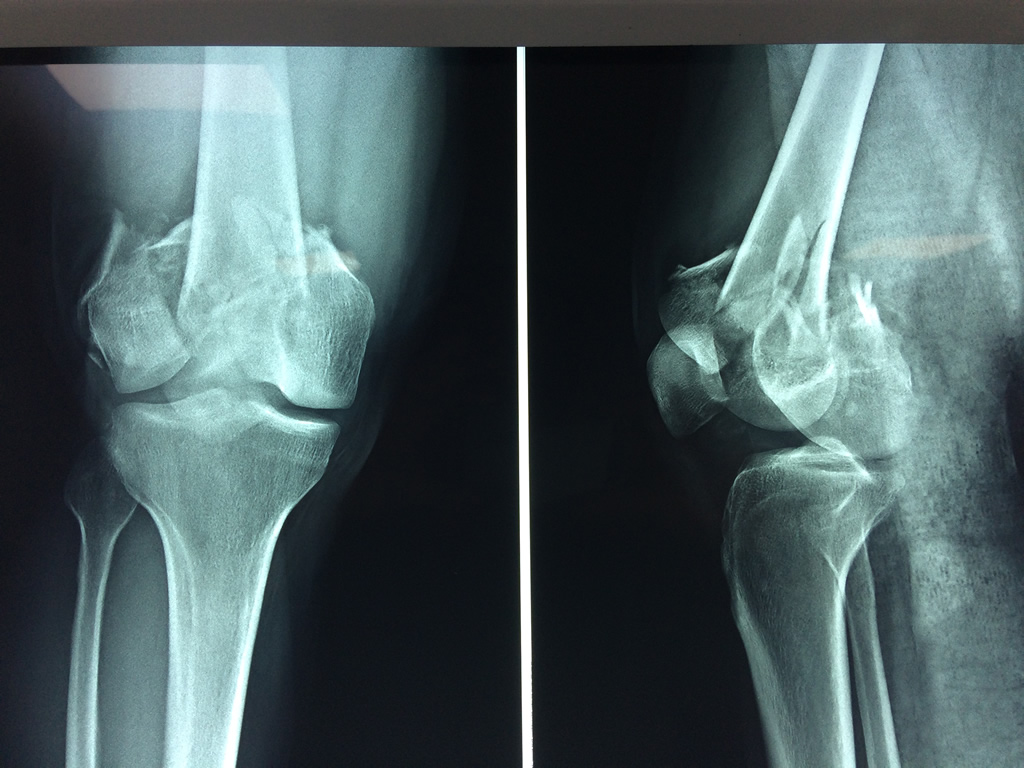

Cirugías de Quiste de Baker